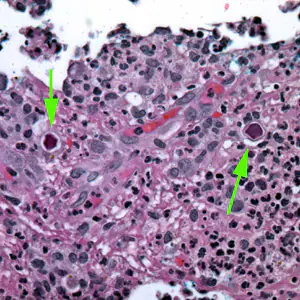

Acanthamoeba spp. cysts.

The cysts of Acanthamoeba spp. are typically 10—25 µm in diameter. The cysts have a two-layered wall with pores: a wrinkled fibrous outer wall (exocyst) and an inner wall (endocyst) that may be hexagonal, spherical, star-shaped or polygonal. Cysts contain only one nucleus with a large karyosome. Cysts may be found in the brain, eyes, skin, lungs and other organs.

Acanthamoeba spp. trophozoites.

Trophozoites of Acanthamoeba spp. are pleomorphic and measure approximately 15—45 µm. They often have multiple spine-like processes called acanthapodia. Trophozoites contain a large nucleus with a large, centrally-located karyosome but no peripheral chromatin. There is no flagellated trophozoite stage in Acanthamoeba spp.